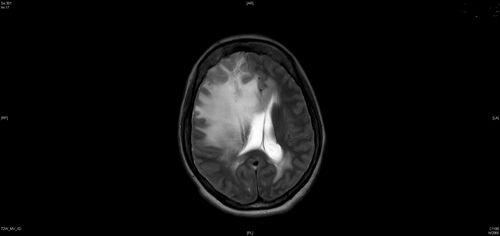

Coats Plus Syndrome - Cerebroretinal microangiopathy with calcifications and cysts (CRMCC)

38 year old female CTC1 positive with Coats Plus Syndrome. This case was published https://pmc.ncbi.nlm.nih.gov/articles/PMC10649444/